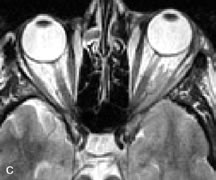

Cavernous hemangiomas appear as well-circumscribed, smooth, usually intraconal masses that are isointense to muscle on T1-weighted images and hyperintense on T2-weighted images (Fig. 12). Patchy early enhancement is typically followed by diffuse, more homogeneous enhancement.39 The internal architecture of the mass, including septation and internal vasculature, may often be appreciated with high-quality orbital imaging.40

Fig. 12. A. T1- and (B) T2-weighted MR scans demonstrate a well-circumscribed intraconal mass causing severe optic nerve displacement. These lesions are usually intermediate in signal intensity on T1-weighted scans and very hyperintense on T2-weighted Images. C and D. Postcontrast fat-suppressed T1-weighted scans demonstrate characteristic patchy intense enhancement that becomes more complete from the initial postcontrast scan (C) to a more delayed scan (D).